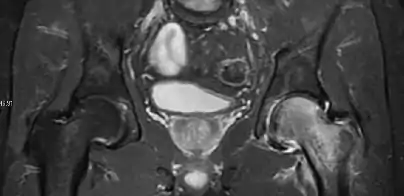

Radiological signs of transient osteoporosis of the hip include localized osteoporosis of the femoral head and neck (Figure 8). Nevertheless, final diagnosis has to be made with MRI to differentiate it from avascular necrosis and from insufficiency or stress fractures of the femoral head or neck. In case of AVN, radiographs can only demonstrate delayed or advanced signs. Staging according to Ficat classification ranges between normal appearance (stage I), slight increased density in the femoral head (stage II), subchondral collapse of the femoral head with or without “crescent” sign (stage III), and advanced collapse with secondary osteoarthritis (stage IV). In the case of stress or insufficiency fractures X-ray sensitivity has been proven to be much lower than MRI, which is currently the gold standard.[1]

Figure 8:

X-ray of a patient with transient osteoporosis of the left hip showing osteoporosis.[1]

Coronal stir imaging in transient osteoporosis, showing diffuse edema.[1]